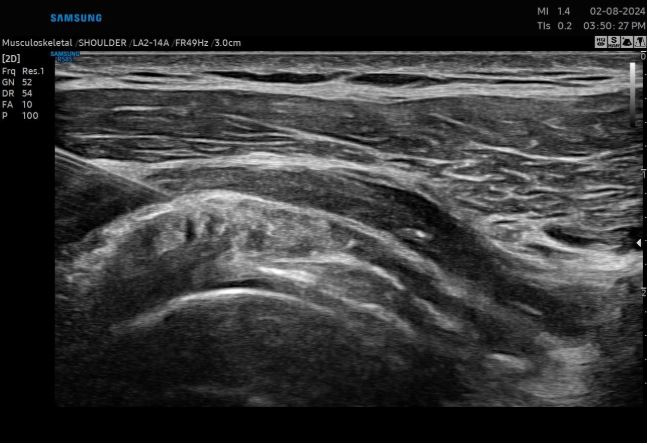

Each treatment begins with a thorough evaluation, including imaging and diagnostic tests, to identify the exact source of shoulder discomfort. Precision-guided injections deliver regenerative solutions directly to the affected area, promoting tissue repair, reducing inflammation, and supporting long-term shoulder stability for daily activities and athletic performance.

From diagnostic ultrasound to image-guided injections, every step of your shoulder care is performed with high-level precision and modern technology, ensuring accurate treatment delivery and better outcomes.